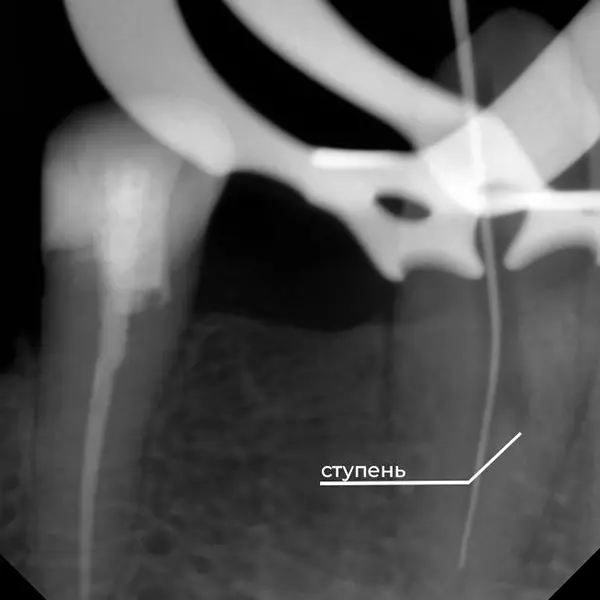

Завершающий этап:

- Стоматологический порошок для ретроградного пломбирования: специальный порошок использовался для перекрытия сформированной “ступени” (изгиба или резкого изменения конусности), обеспечивая герметичность.